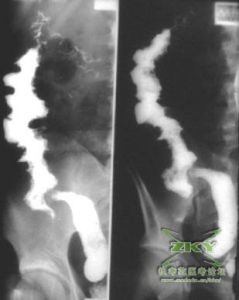

1、X線表現對可疑十二指腸結核的患者,需行上消化道鋇餐檢查,在增生型十二指腸結核的患者,常見X線表現為不同程度的管腔狹窄,多為腔外腫大淋巴結壓迫所致,後者可致梗阻部位出現“刀切”征,或十二指腸圈擴大,表現類似腸系膜上動脈壓迫綜合徵,梗阻近端腸管擴張。少數患者表現為腔內狹窄,黏膜皺襞呈息肉狀改變。潰瘍型患者可有球或球後潰瘍,潰瘍多較小,不易顯示,但多伴有十二指腸黏膜皺襞增厚,管腔痙攣和狹窄。

影像學檢查(l)因潰瘍常較小而不易顯示,但局部“激惹征”顯著,病變範圍長短不一。

(2)腸腔殘留鋇劑時,顯示黏膜皺襞粗亂破壞,有頻繁的往返蠕動。

2、增殖型:

(1)病變範圍較短,腸管狹窄變形,黏膜皺襞呈息肉狀改變。

(2)由於腸外腫大淋巴結壓迫推移,使十二指腸圈擴大,受壓移位。

(3)發生梗阻時,病變以上腸管擴張。